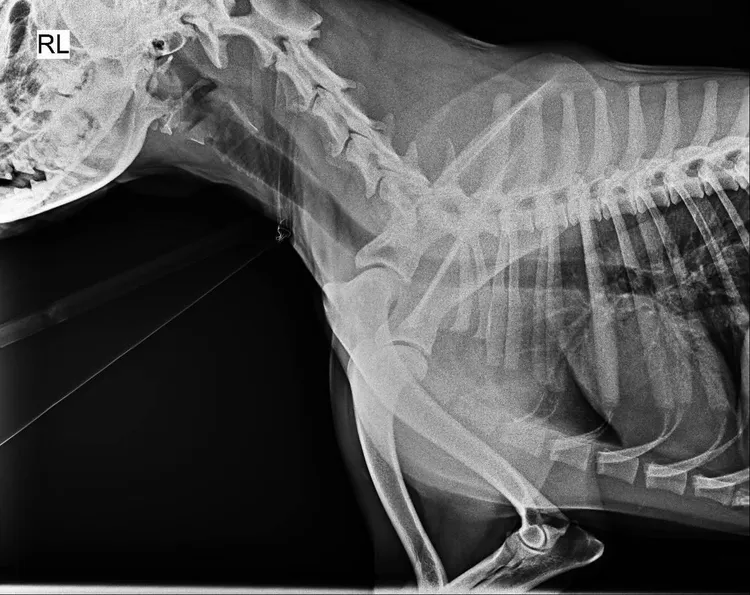

送醫的黑狗沒有明顯傷勢,也沒有骨折,市議員江和樹懷疑遭調包。江和樹提供

黑狗經X光檢查沒有骨折。江和樹提供